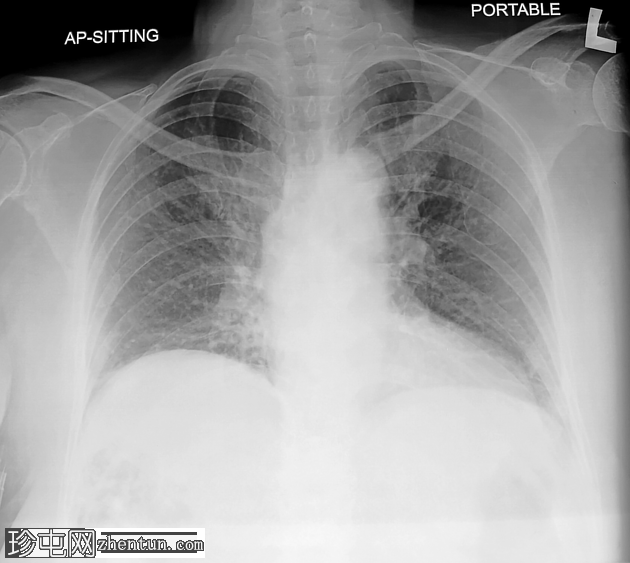

CT

轴位

非增强

肝段 6 和 7 可见多房性积液,呈环状强化

积液内可见多个气体腔

破入肝包膜下间隙,可见肝包膜下积液及气体腔

壁层腹膜与前腹壁之间可见另一局灶性积液

肝段 7 的肝内胆管局灶性扩张(0.3cm),内含气体腔

其他肝内胆管和肝外胆管均正常

胆囊缺失,可能由于既往胆囊切除术所致

无游离液体。

双侧肾皮质囊肿

轻度右侧胸腔积液伴邻近肺不张

超声表现符合气肿性肝脓肿。数小时后进行的肝脏增强 CT 多期扫描显示气肿性肝脓肿破裂。